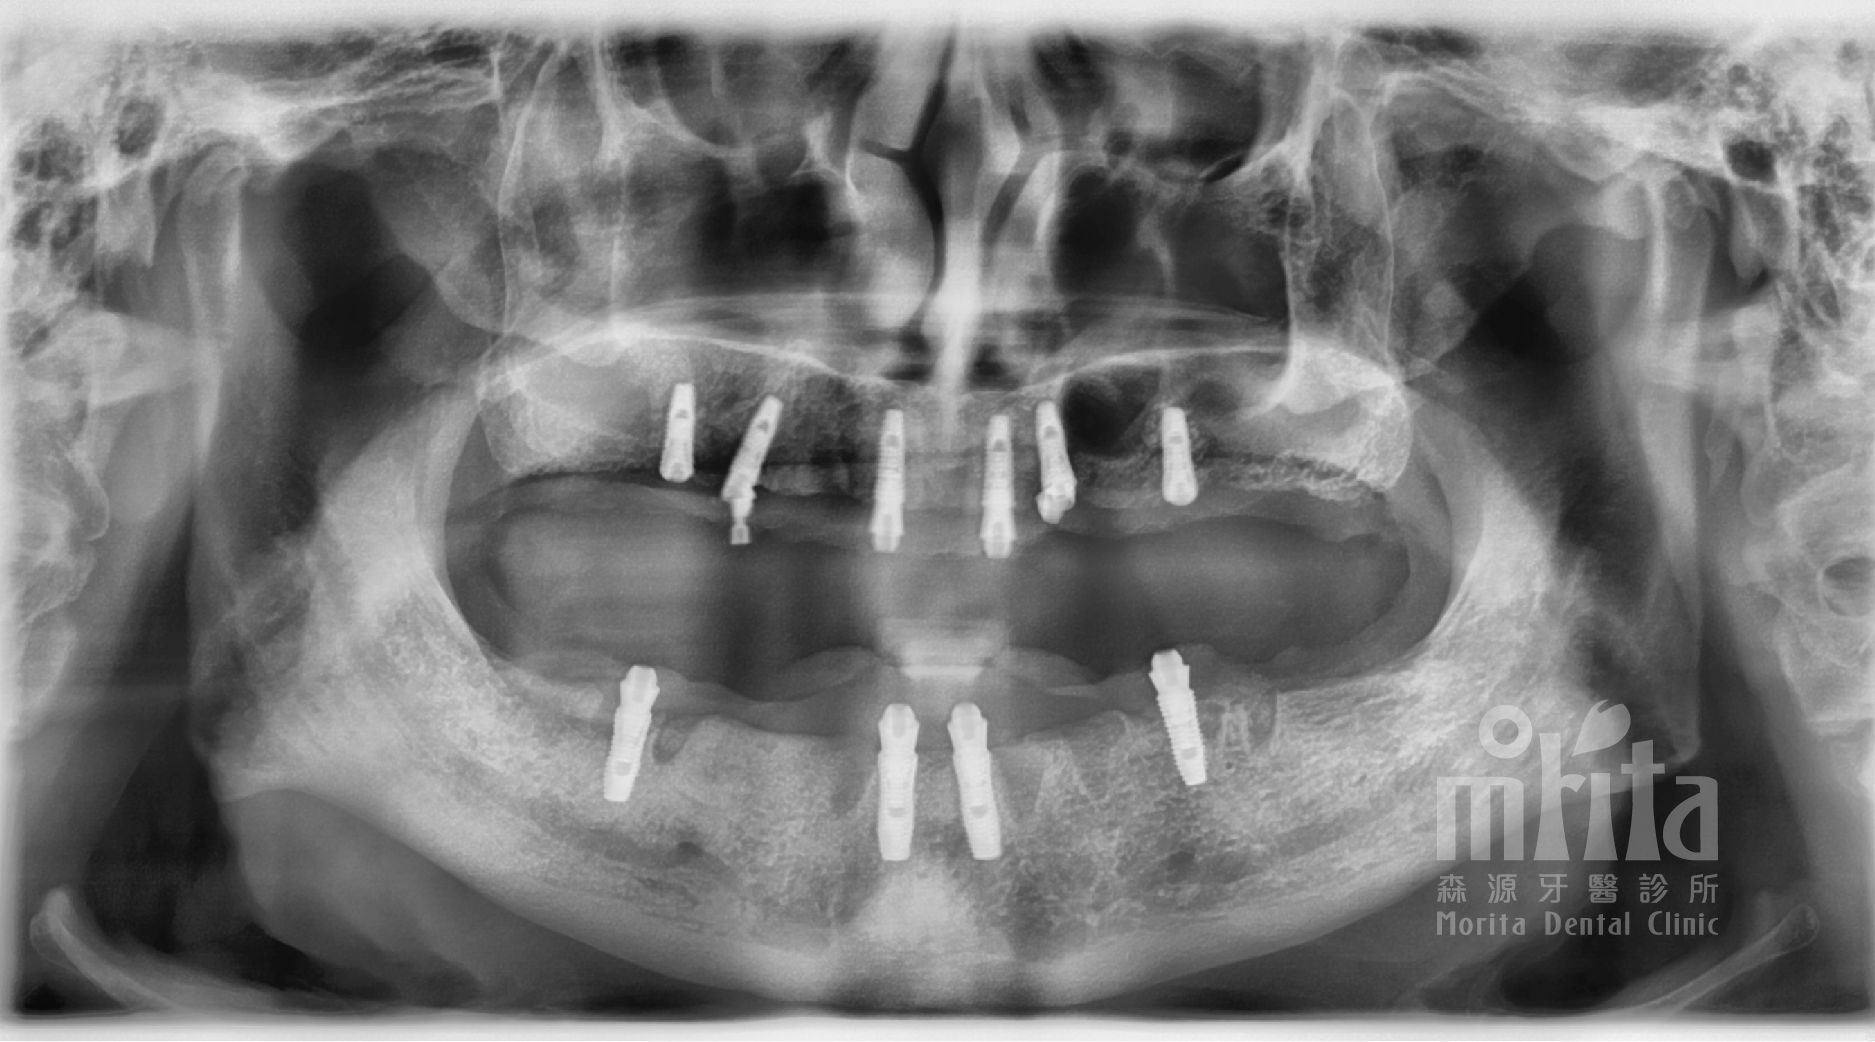

經過完整的事前評估與治療計劃說明,賴伯伯對於森源的醫療團隊感到十分有信心,於是開始進行一日假牙治療。